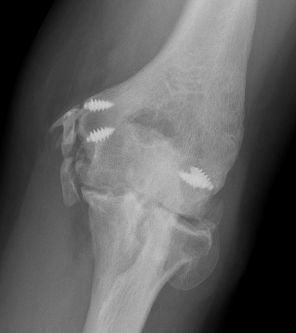

Xray

Elbow HOHOElbow Myositis Ossificans

HOHO